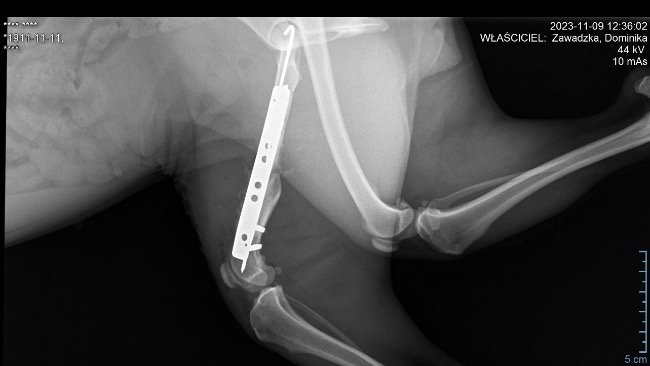

Czas przedstawić Fifi. Suczka bytowała na stacji cpn, najprawdopodobniej tam została potrącona. I tak ze złamaną nogą bytowała dalej na ulicy.Kiedy trafiła pod opiekę Piotra miała anaplazmoze - chorobę odkleszczową i na tym trzeba było początkowo się skupić.Kiedy trafiła do Zacisza nadal utykała. Zostały wykonane zdjęcia rtg i okazało się, że złamanie jest stare, częściowo zrośnięte, ale noga jest krótsza i może jej doskwierać przez resztę życia dlatego została podjęta decyzja o operacji.

Zabieg się udał, teraz staje na rzęsach, żeby przyprawić mnie o zawał próbując brykać pomimo zakazu lekarza!Po 6/8 tygodniach zostaną usunięte druty i ta młoda, radosna dziewczyna będzie mogła ruszać w świat!